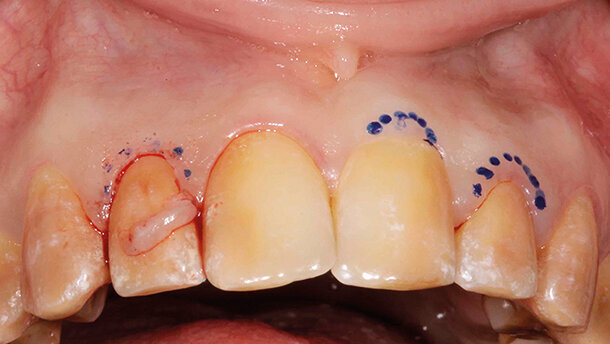

Prima della terapia definitiva sono state eseguite delle correzioni chirurgiche dei settori posteriori per azzerare difetti parodontali ossei (Figg. 2a, 2b) o ridurre l’alterata eruzione passiva (Figg. 2c, 2d). Una volta ottenuta la guarigione dei settori posteriori (Figg. 3a, 3b), sono state eseguite delle correzioni estetiche del settore frontale (Fig. 4).

Una paziente affetta da amelogenesi imperfetta generalizzata (Figg. 1a, 1b) aveva richiesto in età adulta un trattamento estetico. La paziente è stata seguita in età evolutiva con terapie conservative e sottoposta a terapia ortodontica, che aveva ottenuto rapporti di prima classe.